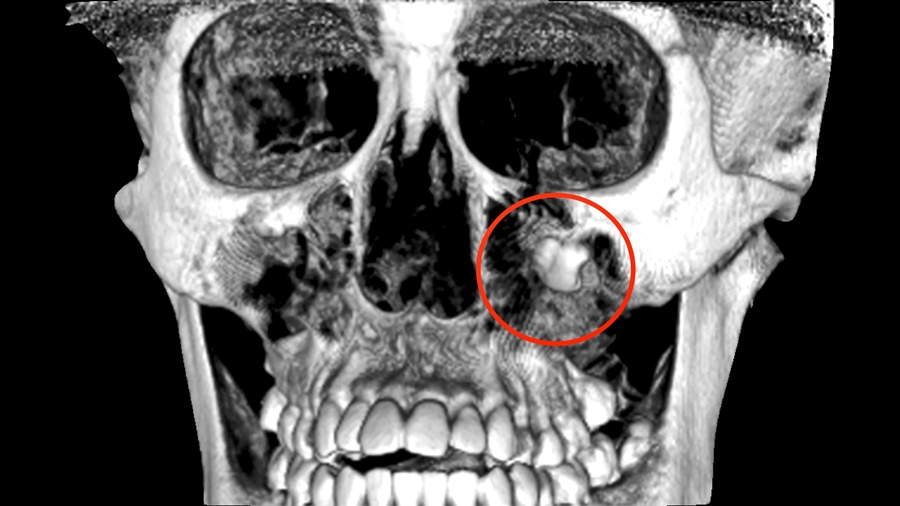

An 18-year old woman went to the hospital for acute cellulitis, and the doctors found that she has a wisdom tooth growing below her left eye, close to the bridge of her nose, and it's causing a growing cyst that is close to her eye socket. Doctor is worried that the growing wisdom tooth could add pressure to her eye and might cause her to lose vision. It took more than a year to gradually remove the tooth. This is the first documented case of a wisdom tooth growing beneath a person's eye socket. The reason behind the odd position cannot yet be determined.

A wisdom tooth is growing close to the bridge of the nose, just one centimeter away from the patient's left eye. The doctor is quite surprised when he saw the X-Ray photo and found that the wisdom tooth isn't growing at a normal position. The tooth has caused a cyst which led to acute cellulitis. Lulu, the 18-year old patient was preparing for her university entrance exam, and had no idea of how serious her condition was.

The doctors said that the wisdom tooth that doesn't grow at its usual place has caused tooth impaction. However, there has never been a documented case in Taiwan in which a patient has a wisdom tooth right below one's eyes. There have been a few similar cases from other countries. The position of the tooth is very tricky and dangerous, and mistake in the attempt to remove it could damage the patient's eyesight. The treatment lasted for more than a year.

The position of the wisdom tooth is very abnormal. It's below the patient's eye socket and right next to the bridge of her nose. It has caused a large sized cyst. In the first phase of the treatment, we're hoping to reduce the size of the cyst. We have resorted to what is called marsupialization to try to move the cyst away from the tooth.